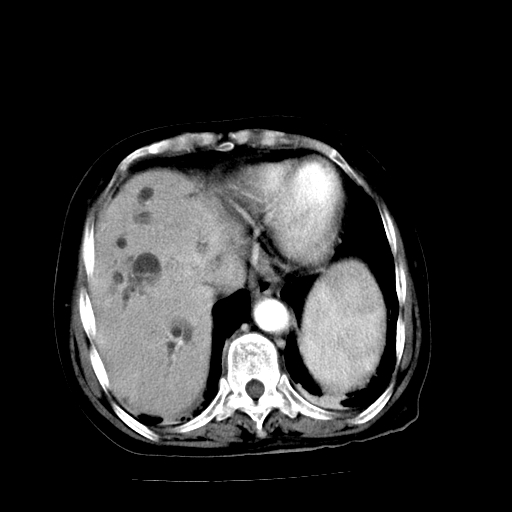

以下是引用卜一在2009-4-7 5:06:00的发言:[br]左右肝内胆管结石伴扩张合并胆系感染;不除外胆管细胞癌可能。支持! [br] [br]

以下是引用随光逐影在2009-4-7 8:21:00的发言:[br]肝内外胆管多发性结石并肝内外胆管扩张;胆系感染。